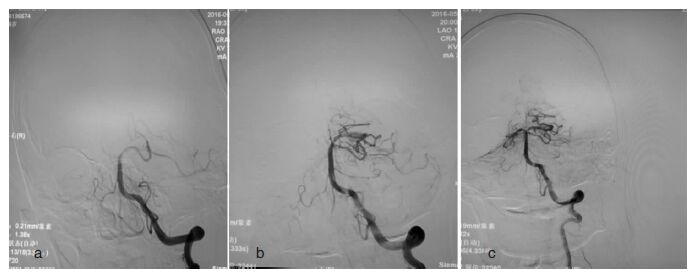

所有患者均采用局部浸润麻醉,躁动明显者给予镇静。全身肝素化,右侧股动脉穿刺,路图下将 6F 导引导管置入椎动脉,造影证实基底动脉闭塞,将导引导管置入V2 段远端,微导丝引导微导管(Rebar-18,EV3 公司,美国)通过闭塞段血管,撤出微导丝,经微导管造影显示基底动脉闭塞远端血管通畅后,将微导丝头端置入较粗大的一侧大脑后动脉,撤出导丝再次微导管造影,确认微导管在血管腔内。行导引导管造影,若基底动脉闭塞再通且狭窄<50%,则不行支架成形术;若基底动脉闭塞再通且狭窄≥50%,球囊(Gateway,Boston,美国)扩张后置入自膨式支架(Wingspan,Boston,美国)或者直接置入球扩支架(Appollo,微创,中国)行狭窄血管成形术。导引导管造影显示基底动脉闭塞未再通者,经微导管置入4 mm×20 mm Solitaire AB支架(EV3 公司,美国),回撤微导管使支架在血管闭塞段展开,停留5~8 min使支架与血栓充分融合,将支架与微导管轻轻撤入导引导管,回撤过程中,回抽微导管内血液,减少血栓破碎后脱落堵塞远端血管的发生风险。再次导引导管造影,了解闭塞血管是否再通,若基底动脉闭塞再通且狭窄≥50%,球囊(Gateway,Boston,美国)扩张后置入自膨式支架(Wingspan,Boston,美国)或者直接置入球扩支架(Appollo,微创,中国)行狭窄血管成形;若基底动脉闭塞再通且狭窄<50%,不行支架成形术;若闭塞血管未再通,可以再重复上述步骤拉栓2次,但总次数不能超过3次。术中造影见图 1。术后严格控制血压,维持在110/70 mmHg左右,警惕出血可能。术后即行Dyna CT,次日复查头部CT,了解有无出血。若确认无出血,未置入支架者术后仅给予低分子肝素钙4 000 μq12h×3 d,扩容;置入支架者,术后给予替罗非班2 ml/h×24 h后改口服双抗6周,拜阿司匹林终生。术后密切观察患者生命体征及神经功能变化,若恶化即行头部CT检查。

| 图 1 基底动脉急性闭塞再通前后造影。a基底动脉上段闭塞;b基底动脉上段部分再通;c基底动脉上段完全再通 |

血管造影发现,基底动脉上段闭塞1例,上段和中段闭塞2例,中段闭塞4例。其中,1例患者(发病4小时治疗,NIHSS 9分)经微导管穿过闭塞段血管后造影发现闭塞血管再通,狭窄<50%,未行支架术,住院1周后出院,3月后改良RANKIN量表(Modified RANKIN Scale,mRS)1分;另有1例患者经过1次拉栓后基底动脉再通且无明显狭窄,2周后出院,3月后mRS 2分;2例患者经过2次拉栓后基底动脉再通且无明显狭窄,其中1例术后复查CT出血,1周后死亡;3例患者经过1次拉栓后血管再通,但血管狭窄均大于50%,其中1例狭窄达90%,3例均行血管支架成形术(Wingspan 2例,Appollo 1例),1例术后出血并3天后死亡。所有7例患者术后即刻Dyna CT均未见颅内出血,但2例患者次日上午复查头部CT有脑干腹侧和丘脑出血,均在1周内死亡。